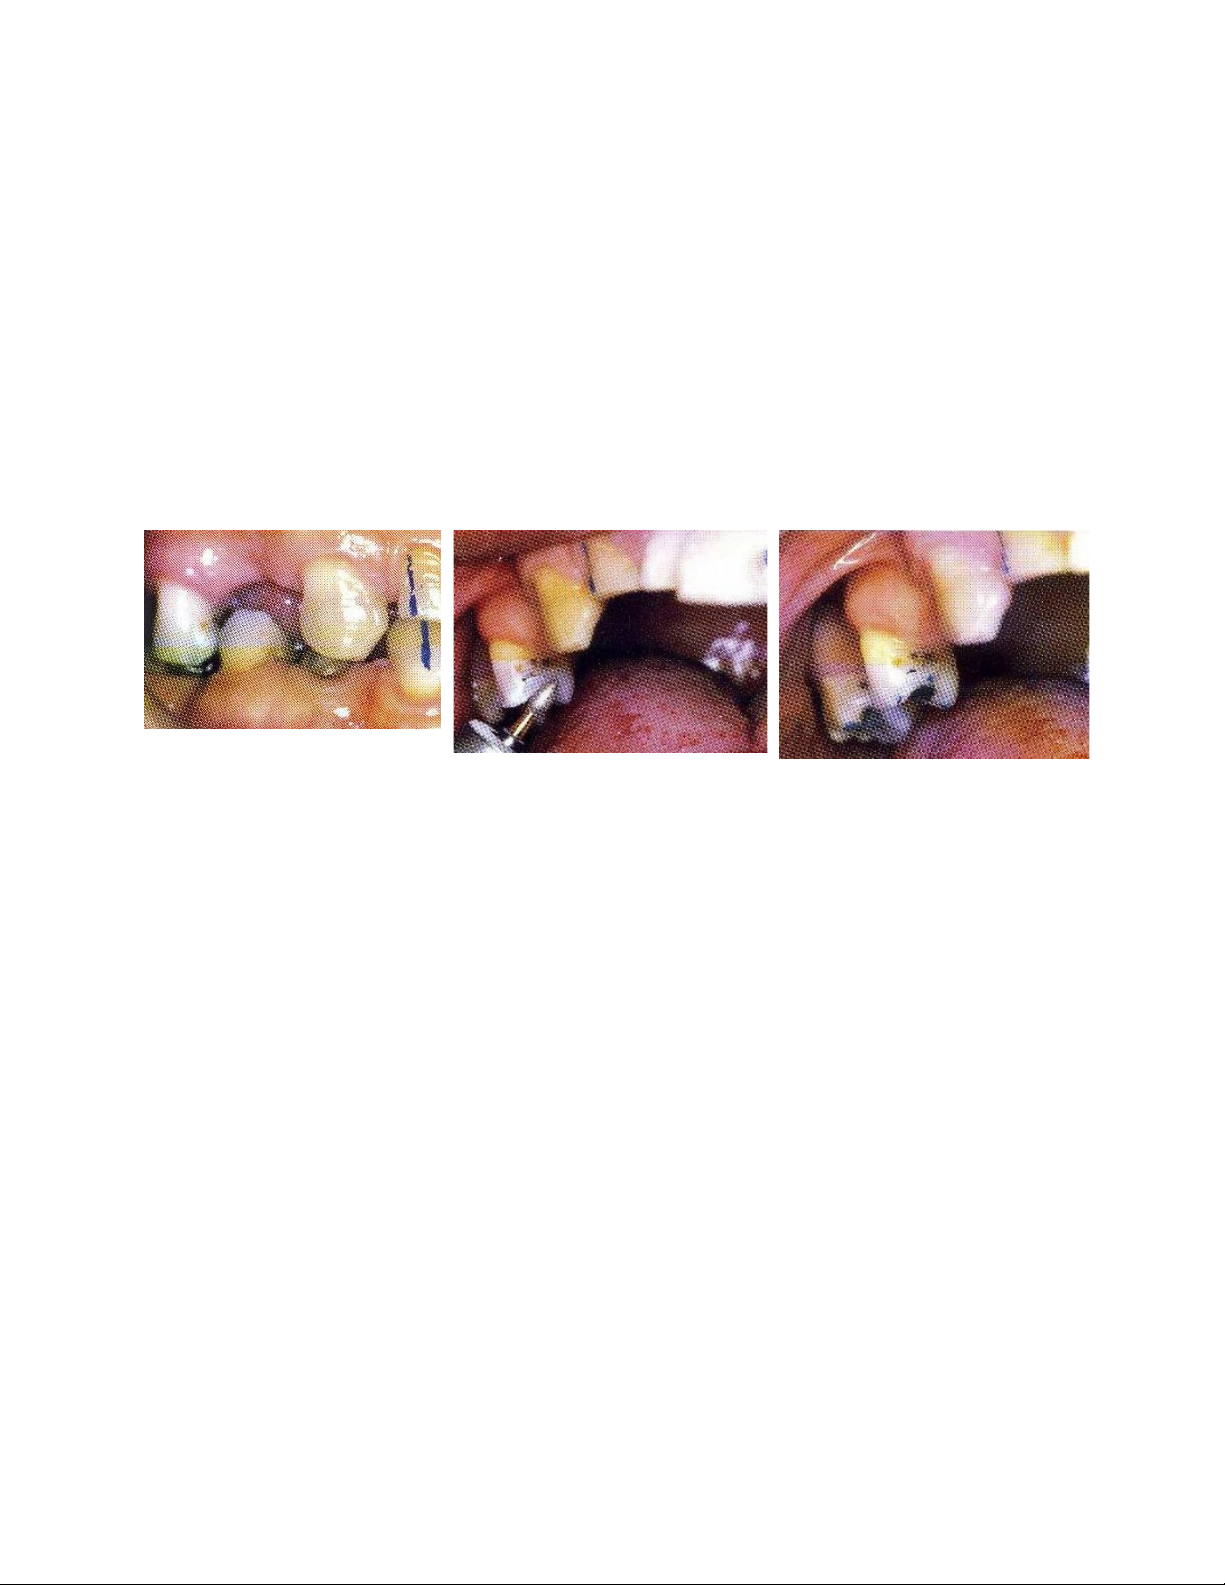

Hình: R15 và 44 trồi do

không có răng đối đỉnh.

Điểm chạm sớm nằm

trên gờ bên răng 15.

Hình: Loại bỏ bằng cách

tạo lại gờ bên nguyên

nhân gây cản trở hành

trình ngậm miệng (nút

chặn được đặt trên răng

cửa khi điều chỉnh khớp

cắn).

Hình: Điểm tựa được bảo

tồn trên gờ bên trong khi

chờ đợi phục hình thẩm

mỹ.